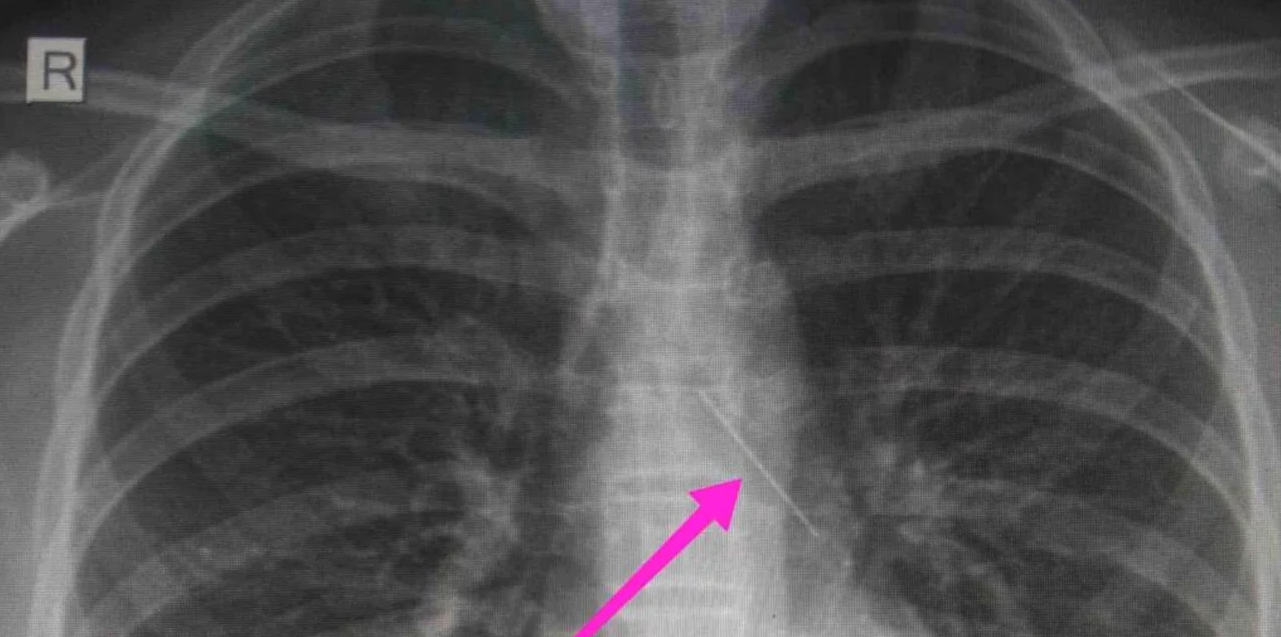

Από την ακτινογραφία θώρακος και την αξονική τομογραφία θώρακος διαπιστώθηκε «η ύπαρξη αιχμηρού μεταλλικού ξένου σώματος στην αναπνευστική οδό (αριστερός κύριος βρόγχος) και όχι στην πεπτική οδό» αναφέρει, μεταξύ άλλων, η ανακοίνωση του νοσοκομείου.

«Χθες 30/1/2022 στις 16:00 στο Τ.Ε.Π. του ΓΝΘ Ιπποκράτειο, προσήλθε ανήλικη συνοδευόμενη από τους γονείς της, μετά από αναφερόμενη κατάποση ξένου σώματος (καρφίτσα). Από την απεικονιστική διερεύνηση που πραγματοποιήθηκε με ακτινογραφία θώρακος αρχικά και ακολούθως με αξονική τομογραφία θώρακος, διαπιστώθηκε η ύπαρξη αιχμηρού μεταλλικού ξένου σώματος στην αναπνευστική οδό (αριστερός κύριος βρόγχος) και όχι στην πεπτική οδό.